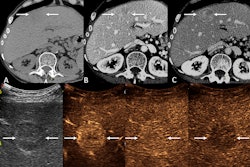

CEUS uses microbubble ultrasound contrast agents that are infused intravenously during an ultrasound exam to enhance images, Strom and colleagues explained. These agents do not contain iodine or gadolinium -- and thus are not nephrotoxic -- and can provide a same-day diagnosis and mitigate delays and costs associated with MR and CT imaging.

In an ICUS statement, Stephanie Wilson, MD, of the University of Calgary in Canada, noted that CEUS "is recognized as the problem solver for all indeterminate CT and MR scans of the liver and kidney." Wilson is co-president of the ICUS.